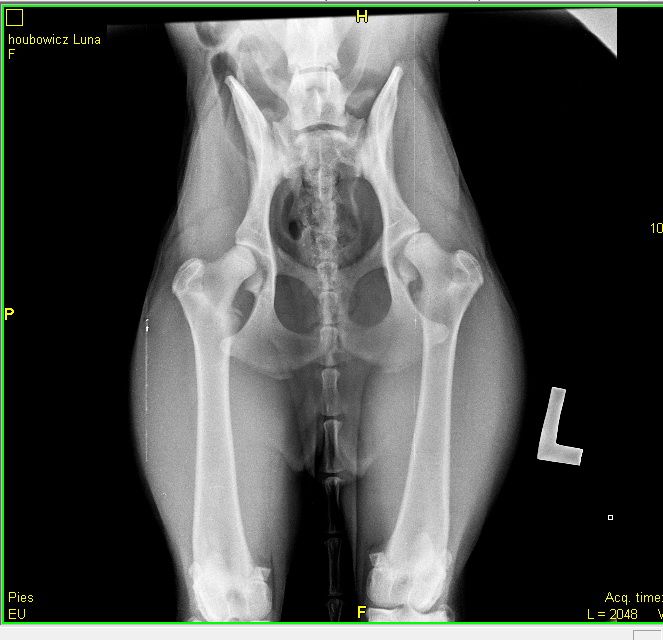

Lunahol Posted October 25, 2012 Posted October 25, 2012 (edited) Hej, opowiem wam w skrócie historię mojej owczareczki. Liczę, że osoby, które mają za sobą podobne problemy wesprą mnie i podzielą się swoimi doświadczeniami. Mam suczkę długowłosą owczarka niemieckiego w wieku niespełna 9 miesięcy (8 miesięcy i 3 tygodnie). W zeszłym tygodniu zgadałam się z naszym wetem na temat kontrolnego zdjęcia RTG stawu biodrowego w celu wykluczenie ewentualnej dysplazji. Było to na zasadzie dmuchania na zimne, bo Lunka w ogóle nie pokazywała żeby coś się działo z jej nogami. Pies jest wulkanem energii, potrafi ganiać do upadłego, skacze, nie potrafi usiedzieć na miejscu, chodzi bez problemu po schodach i nie pokazuje nic co mogłoby wskazywać na jakiekolwiek problemy w biodrami.... A jednak! w zeszłym tygodniu zrobiłam jej RTG i wyszło, że ma straszną dysplazję. Oto jej zdjęcie RTG Mój wet polecił skontaktować się z dr Niedzielskim (jestem spod Wrocławia więc mam rzut beretem) w celu ustalenie jakichś działań, lecz od razu stwierdził, że Lunka kwalifikuje się do operacji, a każdy dzień zwłoki działa przeciwko niej. Ręce mi opadły.... sunia jest okazem zdrowia... nie pokazuje żeby coś ją bolało, jest radosna, wybiegana i zawsze chętna do zabawy, ganiania wron, biegania z innymi psami i co tylko... Dzisiaj byłam u dr Niedzielskiego i w zasadzie wizyta ograniczyła się do ustalenia terminy operacji, bo nic innego nie da rady zrobić:sad: Zabieg który ma być przeprowadzony to DAROPLASTYKA. W chwili obecnej przez najbliższy tydzień mam ograniczyć Lunie ruch do minimum tzn tylko luźny ruch w ogródku, zero spacerów, zero biegania za piłkami, patykami, zero zabaw z innymi psami, pilnować zeby nie skakała i nie obciążała tylnych kończyn. czyli zakaz robienia wszystkiego co mój pies uwielbia robić:(( Po zabiegu przez pierwszy miesiąc Luna będzie mogła tylko leżeć, najlepiej w jakimś małym wydzielonym kącie. Nie wyobrażam sobie tego.... Jeśli ktoś ma jakieś informacje na temat zabiegu daroplastyki to z chęcią posłucham. Jeśli ktoś miał konieczność poddać swojego pupila temu zabiegowi to proszę o rady co robiliście żeby pies usiedział przez ten miesiąc w całkowitym bezruchu. jak przebiegała u Was rehabilitacja po zabiegu?? proszę o jakieś rady jak zajmować psa w czasie 3 miesięcy, w czasie których nie może się praktycznie w ogóle ruszać?? A ja postaram się relacjonować na bieżąco przebieg naszego leczenia. Zabieg odbędzie się w przyszły piątek, czyli 2 listopada. Doła mam strasznego :( Edited October 30, 2012 by Lunahol Quote

Impresja&Simarilion Posted October 25, 2012 Posted October 25, 2012 moim zdaniem to nie jest super zdjęcie do oceny stawów. Po kolanach widać, że jest trochę krzywo pies ułożony. Na tym zdjęciu wydaje się, że lewy staw jest dużo gorszy od prawego. Jestem dopiero na 4 roku wety więc nie jestem ekspertem. Na twoim miejscu przyjechałabym do wrocławia i u specjalisty zrobiła zdjęcia jeszcze raz. Quote

Lunahol Posted October 25, 2012 Author Posted October 25, 2012 Pysia dzięki za posta:) Dzisiaj wet powiedział, że u niej po chodzie widać, że ma problemy ze stawami. Powiedział, że sie porusza nieprawidłowo, ma kończyny w pozycji X i zahacza palcami przy chodzeniu. Nie wiem jak to wytłumaczyć, tak jakby powłóczyła trochę nogami. Ja się nie znam więc tego nie widziałam, a to że dziwnie chodzi tłumaczyłam tym, że owczarki niemieckie przez to kątowanie chodzą trochę śmiesznie... Na zdjęciu mimo wszystko widać, że ma niewykształcone panewki, to widzę nawet ja mimo, że to w zasadzie pierwsze zdjęcie RTG psich bioder jakie widziałam. Z karmieniem suni galaretą z rapek jest trochę problem, bo ona ma nadwrażliwość pokarmową i ma biegunkę po takim jedzeniu. Wcześniej ją karmiłam między innymi rapkami ale straszne miała problem. miała podrażnione jelita przez co załatwiała się z glutem, a teraz ją przestawiłam na suche i jest ok. Z tego samego miotu jeden szczeniak był już operowany. On był odrobinę zatuczony i nogi tego już nie wytrzymały. jak chodził to się co chwilę kładł itd. Jutro zadzwonię do jego właścicieli i zapytam o namiary na ich weta. to się jeszcze z nim skonsultuję. Ja się boję, że z moją teraz nic nie pokazuje ale za kilka miesięcy jak jeszcze trochę podrośnie i nabierze na masie to w końcu posypie się na te nogi. W tej chwili ona jest strasznie chuda, wszystkie kości czuć pod palcami, a za kilka miesięcy jak zacznie rozbudowywać mięśnie to waga jej skoczy i boję się, że tego nogi już nie wytrzymają. Sama nie wiem co sobie myśleć i co robić:( Impresja&Simarilion może się też wydawać ze zdjęcie jest źle zrobione bo jest też krzywo wstawione. Zwróć uwagę na górę foty, że jest zdjęcie przekrzywione. Ale nie ważne faktycznie mogłam dzisiaj kazać zrobić wetowi inne zdjęcie, bo w sumie wzięłam psa na głodaniaka do niego. Impresja a ty jesteś z wrocka?? Quote

Impresja&Simarilion Posted October 25, 2012 Posted October 25, 2012 Zasada jest taka, że na zdjęciu rzepki powinny być w jednej linii, to nie jest wina krzywego wstawienia tylko źle ułożonego psa moim zdaniem. Jestem z worcławia i jesli chcesz moge polecić na pw dobrych lekarzy. bardzo dobrze, że suka jest szczupła. Co do sposobu chodzenia, to bym się nie sugerowała, weterynarz nie musi się znać się na specyfice ruchu każdej rasy zwłaszcza tak udziwnionej jak onek. Quote

Lunahol Posted October 30, 2012 Author Posted October 30, 2012 aganela dzięki ;) Byłam wczoraj u dr Siembiedy na konsultacji. Dr powiedział, że zdjęcie z pierwszego posta faktycznie jest nienajlepiej zrobione, ponieważ nogi są zbyt blisko siebie w związku z czym główki kości biodrowych faktycznie wychodzą trochę na zewnątrz. Jeśli nogi dałoby się troszkę szerzej to nie wyglądałoby to aż tak źle jak jak wygląda. Tak czy inaczej doktorowi wystarczyło takie zdjęcie i stwierdził, że operacja jest zupełnie niepotrzeba jeśli pies nie kuleje, a co za tym idzie nic go nie boli. Więc kamień w sumie spadł i z serca bo właśnie to chciałam usłyszeć :) Powiedział również, żeby przyjechać do niego za pół roku na zdjęcie kontrolne żeby było wiadomo w którą stronę postępuje dysplazja i czy w ogóle postępuje. Powiedział też, że do czasu kiedy pies nie pokazuje, że go boli nie powinno się nic z tym robić, bo bardzo często nawet z gorszymi dysplazjami psy żyły długo i szczęśliwie.. A jeśli chodzi o zalecenia doktora to: -nieprzeciążać psa, czyli nie powinna biegać za rowerem, raczej nie powinna biegać za piłkami i patykami, a z innymi psami to tylko delikatna zabawa. Zakaz chodzenia po nierównym terenie, czyli schody góry itd.. - zbilansowane żywienie, żeby miała wszystkie skłądniki mineralne itd. Moja ma nadwrażliwość ppokarmową więc ją karmię Puriną Pro Plan dla szczeniaków dużych raz z jagnięciną, bo po tym się załatwia ładnie i nie podrażnia jej jelit. - kategoryczny zakaz przybierania na wadze. Pies ma dostawać mniej niż więcej jedzenia i ma być chuda. Doktor obrazowo nam przedstawił dlaczego nie powinniśmy jej operować. Zapytał czy ja dałabym się pociąć tylko dlatego, że mi na zdjęciu wyszła jakaś wada budowy, która mi w ogóle nie doskwiera. No raczej nie :P Cieszę się, że do niego pojechałam, bo w sumie w głowie przed wizytą miałam dokładnie to co on mi powiedział tylko moje rozumowanie było bardziej na chłopski rozum i potrzebowałam żeby jakiś lekarz to potwierdził. Operację odwołałam. Wieczorem wstawię filmik, jak mi się uda, jak moja włochata dyspalzja się rusza. Quote